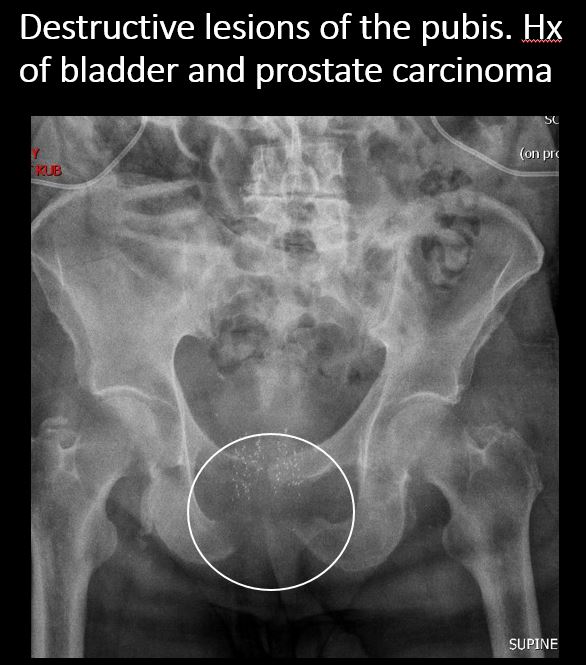

There is a lytic, blastic, or destructive lesion of the spine, pelvis, femurs, or ribs. [Yes/No]